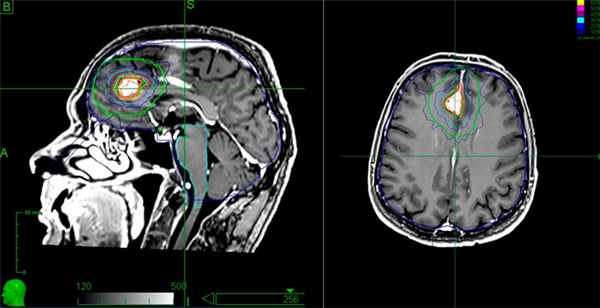

- лучевая терапия на установке Кибер-Нож — современный и малотравматичный метод лечения образований размером до 3.5-4 см. На опухоль воздействуют направленным потоком ионизирующего излучения. Окружающие ткани при этом практически не повреждаются.

Лечение менингиомы. Этапы подготовки мишени для облучения на системе "Кибер-нож”

Кибер-Нож позволяет удалить опухоль без боли и повреждения важных структур мозга. Процедура проводится в амбулаторных условиях без госпитализации пациента, после терапии пациент сразу может ехать домой. В ПЭТ-центре план лечения составляется врачами радиологом и онкологом, что позволяет выбрать наиболее эффективную тактику для конкретного пациента.